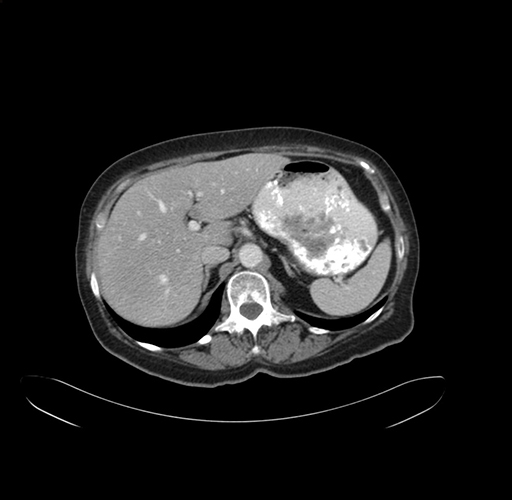

Pre-Chemo: Axial Venous